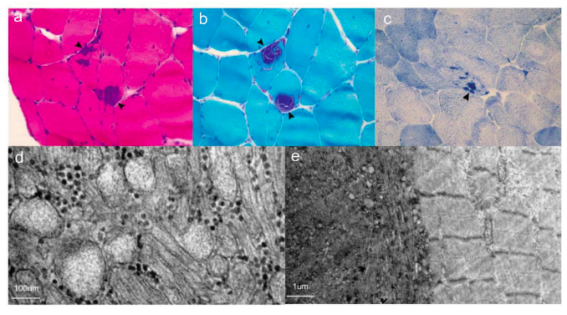

该研究详细记录了国产亚洲精品美女久久久_99久无码中文字幕一本久道_亚洲成AV人影院_亚洲AV影院一区二区三区 狠狠躁夜夜躁人人爽天天不卡_国产激情久久久久影院老熟女_精品性高朝久久久久久久第一医院神经内科收治的SCN4A基因突变相关的离子通道病先证者及其家系的基本资料����、病史��、查体����,行电生理检查����、肌肉活检��、基因分析���。

SCN4A基因突变相关的离子通道病肌肉活检病理变现可见肌纤维中出现管聚集及空洞����。